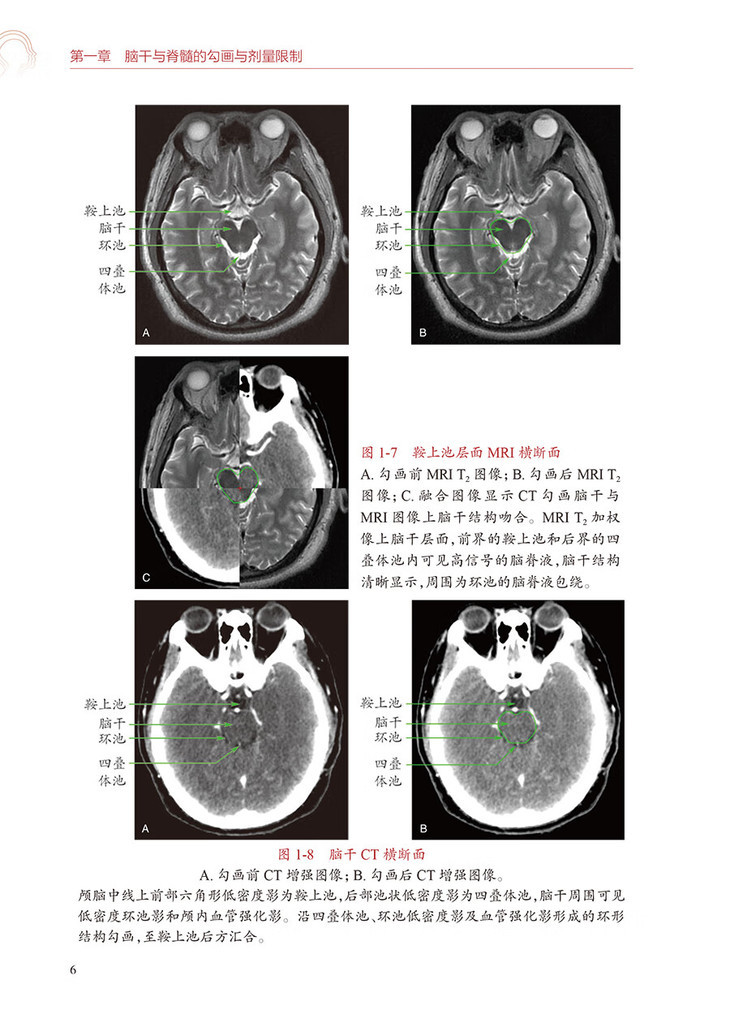

第二节勾画图谱/2